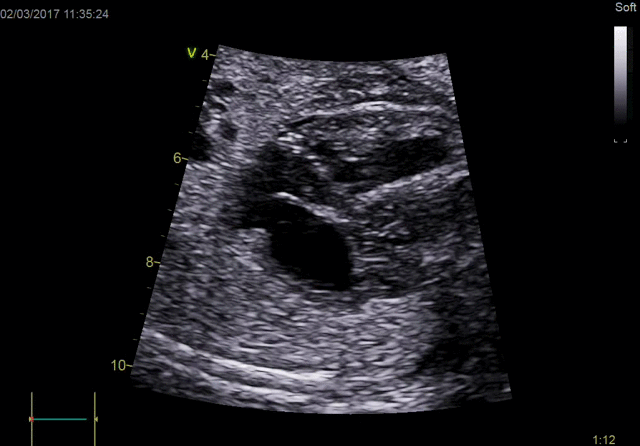

Neonatal Heart Imaging